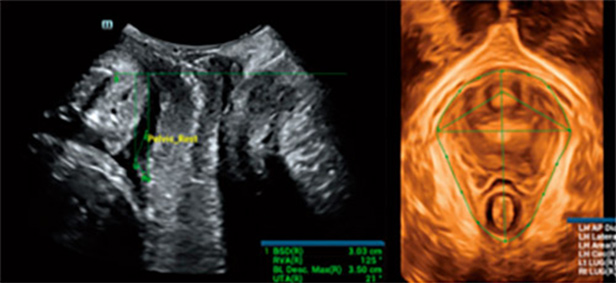

L'Êvaluation de l'emplacement et de la morphologie de l'ensemble des structures tissulaires pelviennes et du hiatus des releveurs constitue l'objectif principal de l'examen Êchographique du plancher pelvien. Cependant, l'examen manuel traditionnel est chronophage et dÊpend de l'opÊrateur, et les Êchographistes inexpÊrimentÊs rencontrent souvent des difficultÊs de localisation. Parallèlement, l'inefficacitÊ de la procÊdure d'imagerie peut multiplier la gêne et l'inconfort pour les patientes. Avec la sensibilisation croissante à la santÊ du plancher pelvien des femmes, il est prÊvisible que la demande d'examens du plancher pelvien par Êchographie augmente. Il est donc impÊratif de dÊvelopper une mÊthode de diagnostic du plancher pelvien par Êchographie plus exacte, plus efficace et plus simple à utiliser.

Mindray a dÊveloppÊ Smart Pelvic, une solution intelligente d'Êchographie du plancher pelvien pour aider les Êchographistes à obtenir rapidement des coupes et des mesures standardisÊes lors d'examens complexes du plancher pelvien et pour amÊliorer l'efficacitÊ du diagnostic. Smart Pelvic peut effectuer automatiquement des mesures pelviennes complètes et offrir une imagerie?3D automatique du hiatus des releveurs, ainsi que des mesures du diamètre longitudinal, du diamètre transversal, de la superficie du hiatus des releveurs et de la taille de la lacune urÊtrale des releveurs. Les Êchographistes peuvent obtenir des donnÊes cliniques complètes pour une Êvaluation exacte en quelques interactions simples, nÊcessitant seulement un tiers du temps des examens traditionnels. En outre, Mindray propose trois normes industrielles principales qui prennent en charge diffÊrents types de sondes et permettent un fonctionnement standardisÊ.

Smart Pelvic